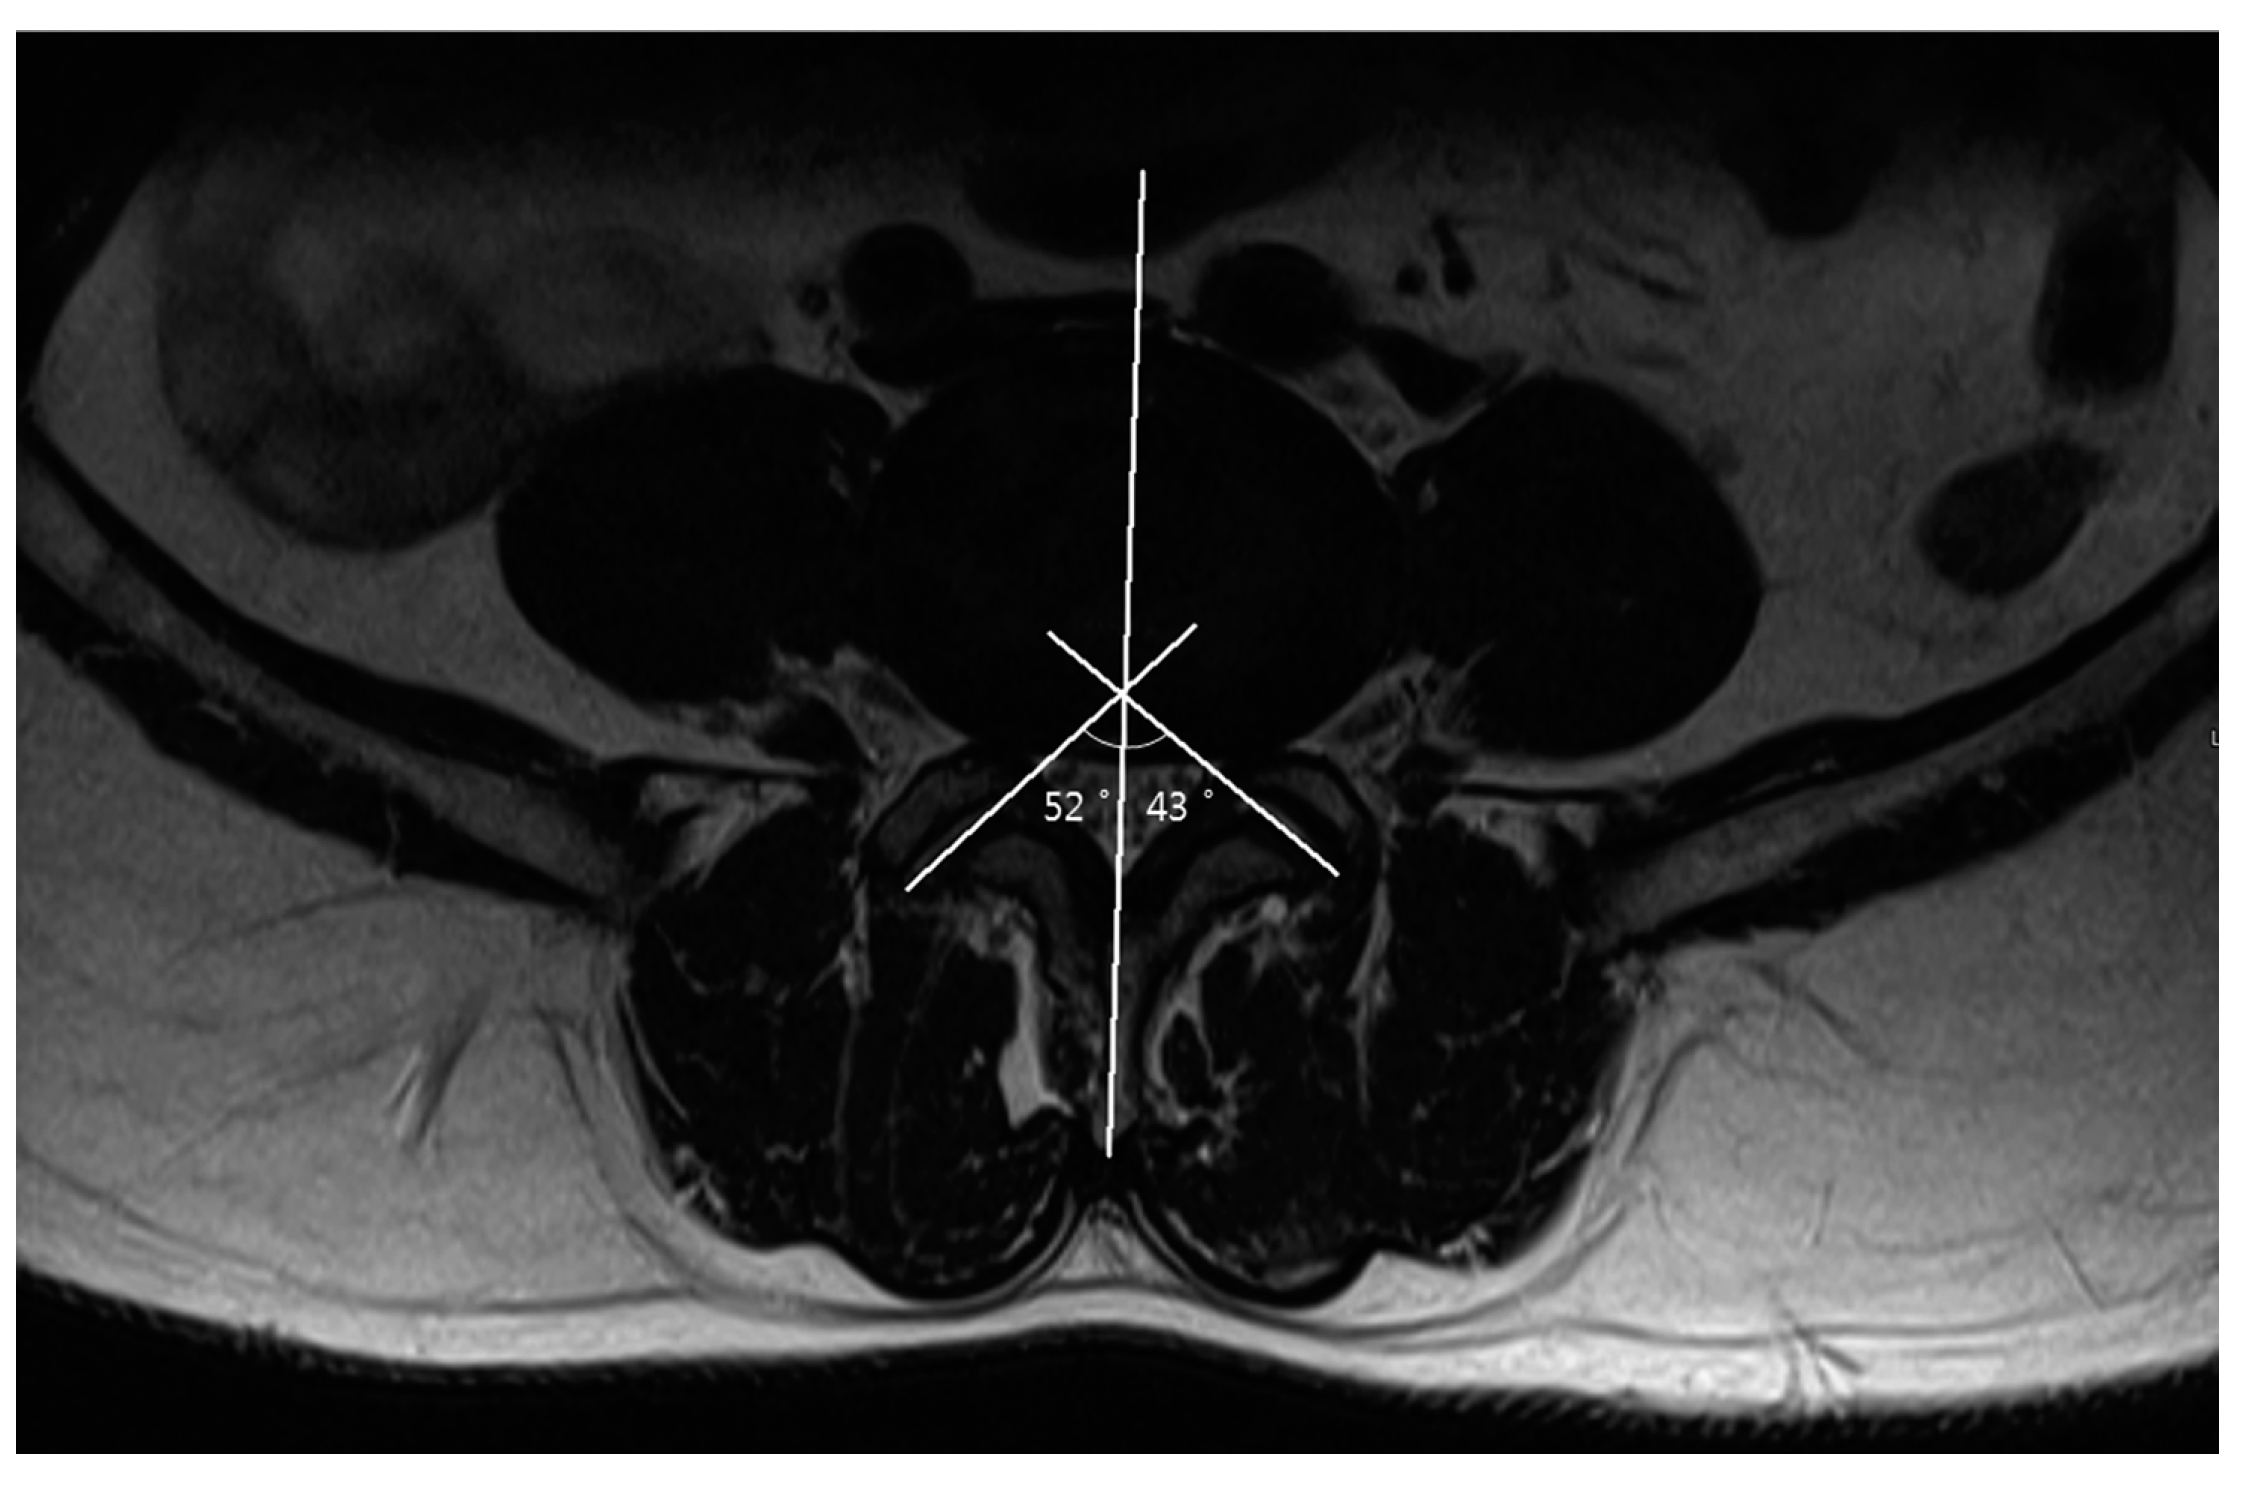

2.4. Measurements

| Facet angle (°) (mean ± SD) | |||

| L3–4 | 38.82 ± 10.74 | 37.07 ± 10.69 | 0.304 |

| L4–5 | 45.15 ± 9.81 | 45.08 ± 9.68 | 0.661 |

| L5–S1 | 47.88 ± 9.04 | 49.44 ± 11.97 | 0.345 |

| Facet angle difference (°) (mean ± SD) | |||

| L3–4 | 7.42 (2.09–14.70) | 6.02 (2.54–9.26) | 0.087 |

| L4–5 | 7.38 (3.00–12.76) | 6.54 (3.27–11.10) | 0.313 |

| L5–S1 | 9.20 (5.00–16.57) | 7.78 (4.33–11.18) | 0.102 |